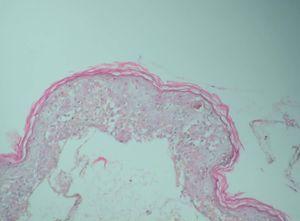

Se realizó una toma de biopsia de una de las lesiones ampollosas y el estudio anatomopatológico reveló un despegamiento dermoepidérmico con necrosis de la epidermis (fig. 2), y en la dermis un infiltrado mononuclear de predominio perivascular.

Fig. 2.—Ampolla subepidérmica con necrosis de los queratinocitos. (Hematoxilina-eosina, ×200.)